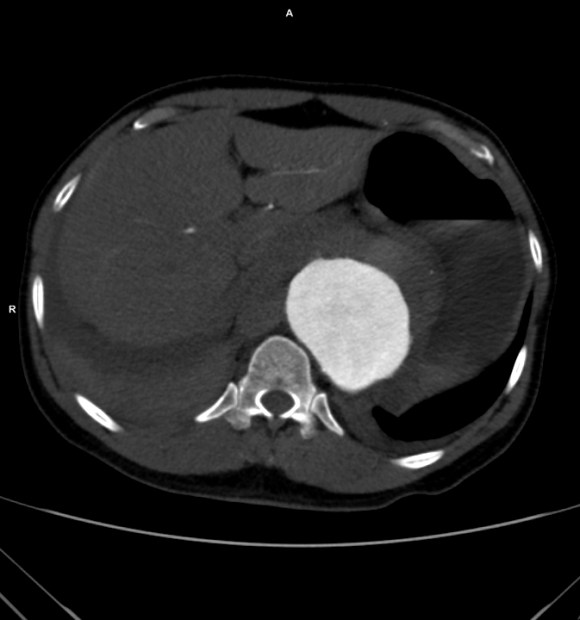

The patient had a 8cm sphere shaped aneurysm arising in the transdiagphragmatic aorta, leaking into the right pleural cavity.

The patient was otherwise a healthy middle aged man with risk factors of smoking and hypertension. The centerline reconstructions showed the thoracic aorta above the aneurysm to be around 20mm in diameter and same below, with the celiac axis and superior mesenteric artery in the potential seal zone of a stent graft. The only plaque seen was around the level of the renal arteries and was focal and calcified. Looking at the list I had made as a comment to the Linked-In post, I realized that I really only had one viable option.